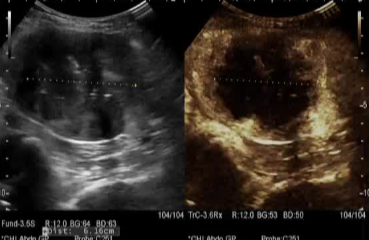

肌瘤变化:消融后的肌瘤不会立即消失,而是在3-6个月内逐渐萎缩、吸收,症状随之改善。吸收速度因人而异。

随访:术后需要定期(如1、3、6、12个月)进行超声或MRI复查,评估肌瘤缩小情况和疗效。